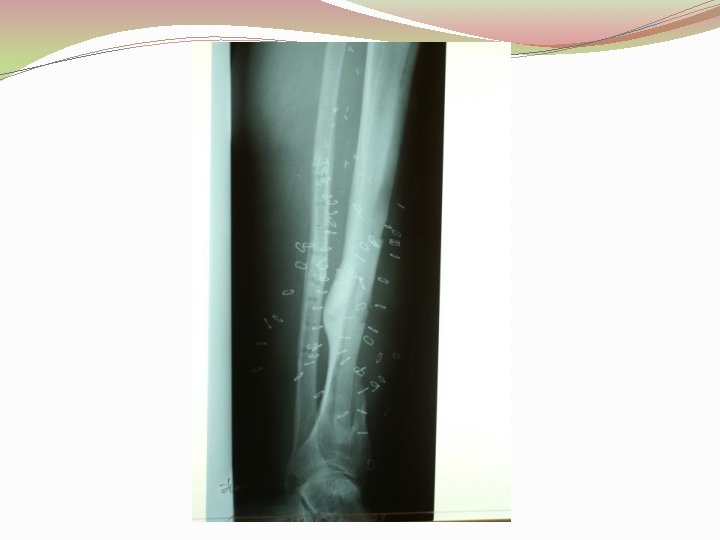

Biežums �Patzakis et al vaļēja tībijas gadījumā nelietojot antibiotiķus osteomielīta attīstība ir 24%, lietojot tikai 4, 5% � 2 -7% Stobra kaulu lūzumu gadījumos attīstās osteomielīts Lucian Fodor, Zvi Horesh, Alexander Lerner, Ytzhack Ramon, Isaac J. Peled, Yehuda Ullmann, The Distally Based Sural Musculoneurocutaneous Flap for Treatment of Distal Tibial Osteomyelitis, Plasic and Reconstuctive Surery 119: 2127, 2007.

Ķirurģiska ārstēšana Osteomielīta pacientiem jāveic radikāls debridement ķirurģiski, kas ietver visu procesā iesaistīto audu rezekciju: �Mīksto audu rētas rezekcija �Cīpslu kalcinātu rezekcija �Distantu sekvestru rezekcija �Kaula rezekcija līdz vizuāli veseliem audiem – readzama punktveida asiņošana ´Paprika sign’. Bogdan Maciuceanu, Lucian Jiga, Alexandru Nistor, Jenel Marian Pastrascu, Mihail Ionac Chronic Osteomyelitis of Long Bones Timisoaral Medical Jornal, 2005

Debridement Os konstrukciju evakuācija Biopsija un mikrobioloģija Dobuma slēgšana Antibakteriāla terapija Stabilizācija (Ārējā fiksācijas aparāts) Maina vai apstiprina antibakteriālo terapiju Mīksto audu rekonstrukcija 6 nedēļas antibakteriāla terapija (pēc debridement) Pseidartroze Konsolidācija Atkārtot ārstēšanu Luca Lazzarini, Jan T. Mader, Joson H. Calhaun Osteomielitis in Long Bone, The journal of bone&joint surgery, Volume 86 A, nr 10, 2004